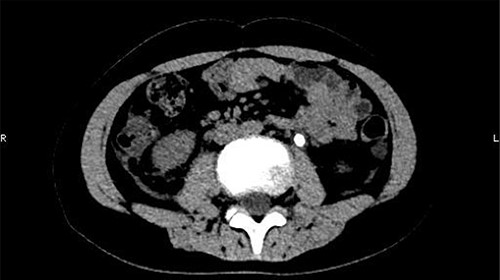

The patient was confined to bed, fasted and prescribed a daily intravenous infusion of cefazolin sodium pentahydrate, 2.0 g for 10 days. CT showed some irregular high-density shadows were present in the left renal pelvis (Fig. 1), and a small strip of high-density shadow was apparent in the bladder cavity (Fig. 2). Blood tests showed no abnormality in serum calcium concentration. Cefazolin sodium pentahydrate was discontinued immediately.

A small strip of high-density shadow was present in the bladder cavity.